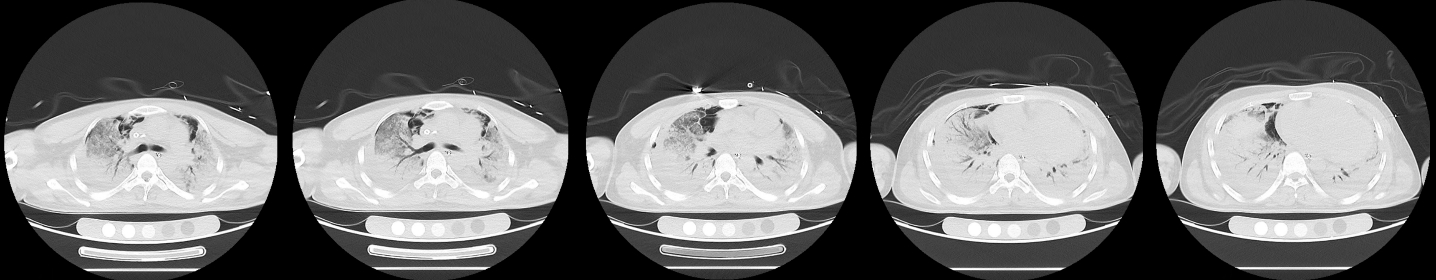

同时给予镇痛、镇静联合肌松,去甲肾上腺素泵入维持血压,俯卧位通气,B某入院后出现高热,经验性给予美罗培南联合万古霉素抗感染治疗,后降阶梯调整为哌拉西林他唑巴坦联合万古霉素治疗;C某抗感染方案为经验性使用万古霉素联合哌拉西林他唑巴坦治疗,痰培养出鲍曼不动杆菌后改为替加环素、头孢哌酮舒巴坦及万古霉素治疗;根据《刺激性气体中毒诊治专家共识》[5]中关于重症患者的治疗措施,同时给予2人泮托拉唑抑酸护胃,氨溴索、富露施化痰、甲泼尼龙抗炎、西维来司他纳及乌司他丁清除炎性介质,维生素C抗氧化、保肝、输血补液,纤支镜吸痰及肺泡灌洗,维持水电解质平衡及营养支持治疗,特别考虑到肺损伤情况,在使用有创通气时给予超保护性通气策略[5, 7];2人仍先后出现气胸、纵膈气肿,行胸腔闭式引流;持续V-V ECMO治疗15 d后,肺部纤维化不可逆转,高分辨率CT肺纤维化评分 > 75%(图 3、4),符合终末期肺病标准,有肺移植指征[8],经评估后2人顺利完成病变肺组织切除(图 5),双侧序贯肺移植,术后患者复查胸片肺部恢复正常(图 6),2位患者术后气管切管接呼吸机辅助通气,并给予泼尼松、他克莫司、吗替麦考酚酯抗排异治疗,其余根据病情给予万古霉素调节肠道菌群、抗感染、保肝、抗凝、呼吸康复锻炼等治疗,后顺利脱机、拔除气切套管,病情稳定出院,后续规律复查胸部CT(图 7)恢复良好。

更主要的是,上述氧化应激与炎症反应是驱动肺组织不可逆纤维化的重要始动因素。在毒性损伤的持续刺激下,上皮-间质转化过程被异常激活[5, 13],肺泡上皮细胞转化为成纤维细胞,导致成纤维细胞增生及细胞外基质过度沉积[13]。因此在中毒后短期内即出现暴发性、不可逆的肺纤维化[14]。其直接临床后果是肺顺应性严重丧失,肺组织脆性显著增加。这正是在救治过程中,即便本团队应用了超保护性通气策略严格控制潮气量、平台压及驱动压,两例重症患者仍不可避免地发生了气胸和纵隔气肿的根本原因。此时,机械通气本身已成为气压伤的风险来源[6],凸显了毒性肺损伤的极端严重性。